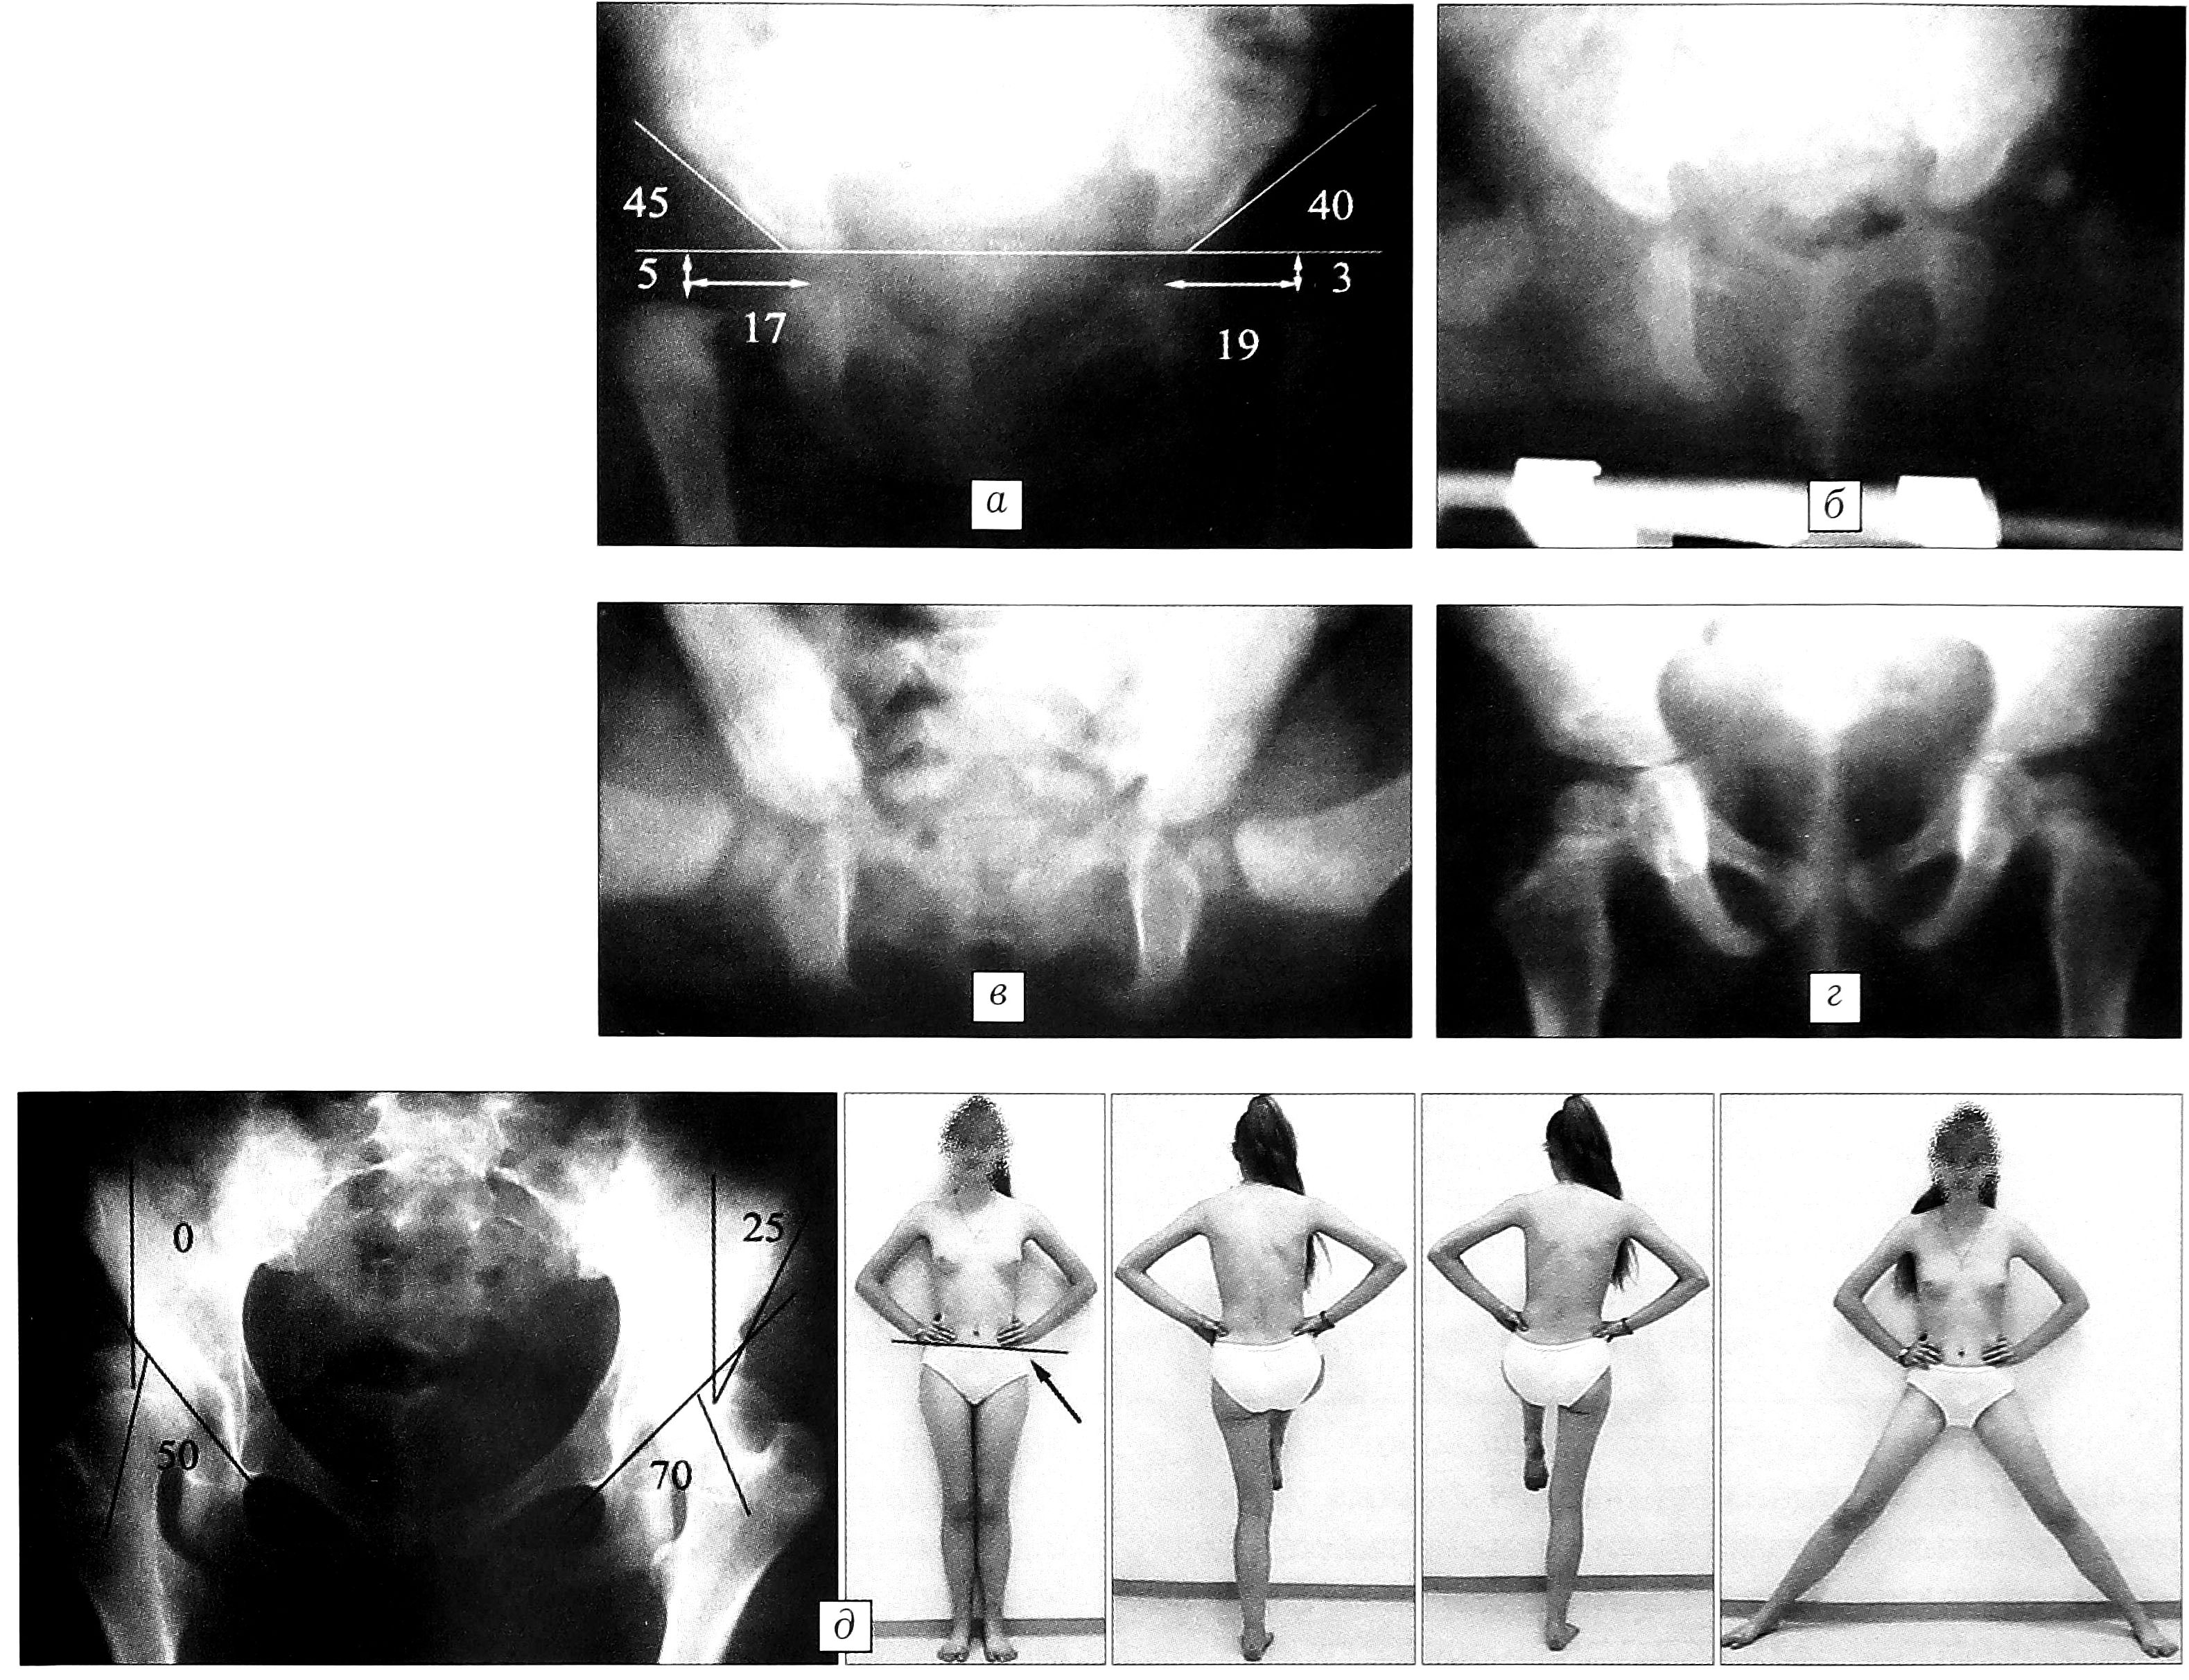

Анализ случаев неустраненного вывиха бедра при лечении с помощью подушки Фрейка выявил, кроме того, несоблюдение показаний к применению этого ортопедического пособия — назначение его детям с высоким смещением головки бедра. Очевидно, что фиксация нижних конечностей подушкой Фрейка целесообразна только при дисплазии тазобедренного сустава без краниального смещения головки бедра. При истинном же вывихе, устранив контрактуру и добившись полного разведения бедер, вправить головку в вертлужную впадину в таком положении не удастся (рис. 1). Применение отводящей шины может быть оправданно также при наличии только дисплазии тазобедренного сустава без децентрации головки бедра. В других случаях лечение этим методом бесперспективно и, следовательно, ошибочно. Примером может служить следующее наблюдение. Больной Д. с двусторонним врожденным вывихом бедер при надацетабулярном расположении головок бедренных костей по месту жительства было назначено лечение в отводящей шине. Контрольная рентгенография показала, что головки бедренных костей располагаются вне вертлужных впадин, однако фиксация в отводящей шине продолжалась. При обращении в ЦИТО в возрасте 7 мес надацетабулярный двусторонний вывих сохранялся (рис. 2).

Рис. 1. Пример неадекватного лечения в отводящей прокладке типа подушки Фрейка. Больная А. 3 мес, диагноз: врожденный надацетабулярный вывих головки бедра.

Рис. 2. Пример неадекватного лечения в отводящей шине. Больная Д., диагноз: врожденный надацетабулярный вывих бедер. а — в возрасте 1 мес; б — рентгенологический контроль в возрасте 7 мес в функциональной гипсовой повязке: головка левого бедра располагается за задним краем вертлужной впадины; в — при обращении в ЦИТО в возрасте 1 года 3 мес: вывих в левом тазобедренном суставе сохраняется.

Рис. 6. Отдаленный результат лечения больной В. (первая группа). а — в возрасте 8 мес: ацетабулярный вывих головок бедренных костей; б — лечение в функциональной гипсовой повязке: через 1 мес после начала лечения достигнуто вправление; в — в возрасте 1 года 6 мес: развитие тазобедренных суставов соответствует возрастной норме; г — клинико-рентгенологический результат в возрасте 10 лет: полная компенсация функции тазобедренных суставов.

Рис. 7. Отдаленный результат лечения больной Д. (вторая группа). а — в возрасте 4 мес: ацетабулярный вывих головок бедренных костей; б — в возрасте 7 мес: неадекватное лечение в отводящей шине (до поступления в ЦИТО), головки бедренных костей располагаются вне вертлужных впадин; в — в возрасте 9 мес: при лечении в функциональной гипсовой повязке достигнуто вправление; г — в возрасте 1 года 9 мес: развитие тазобедренных суставов соответствует возрастной норме; д — клинико-рентгенологический результат в возрасте 13 лет: субкомпенсация функции тазобедренных суставов; формирование остаточного подвывиха головок бедренных костей, больше выраженное справа.